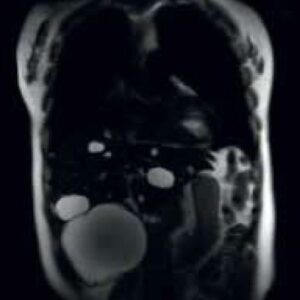

Body Imaging

The Body Suite is specialized for Clinical body examinations.